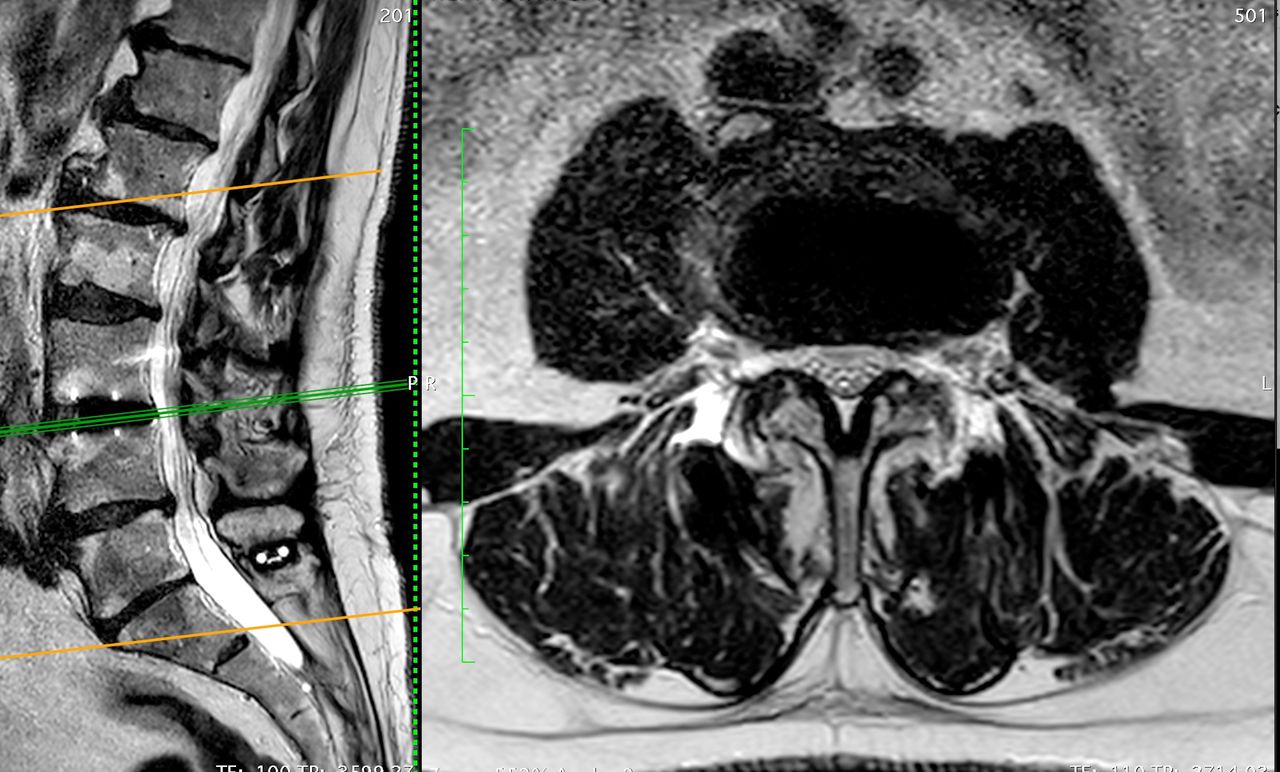

Sono specializzato anche nel trattamento delle deformità dell'adulto, quali la scoliosi e lo sbilanciamento sagittale, che tratto con tecniche mini-invasive e approcci anteriori e laterali (ALIF e XLIF rispettivamente), in grado di non violare la muscolatura e garantire un rapido decorso post-operatorio, diminuendo il dolore legato agli accessi chirurgici. Utilizziamo di routine il monitoraggio neuro-fisiologico per ridurre al minimo il rischio di danni ai tessuti nervosi.